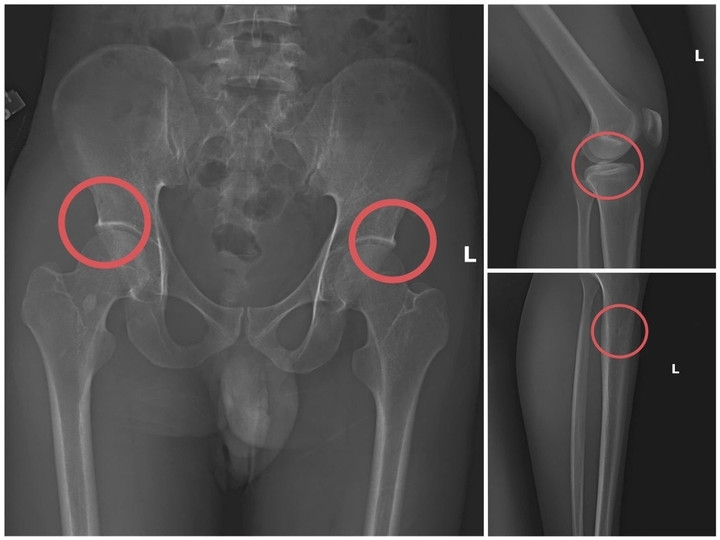

Công an tỉnh Phú Thọ vừa triệt phá đường dây tự gây thương tích có tổ chức, thủ đoạn tinh vi nhằm trục lợi hơn 6 tỷ đồng từ nhiều công ty bảo hiểm nhân thọ. Kẻ cầm đầu, chủ mưu là Tạ Minh Châu (SN 1995, cựu cán bộ Trung tâm Y tế huyện Cẩm Khê).

Dựa vào hiểu biết chuyên môn về y tế của cán bộ y tế, các đối tượng bàn bạc phân công thống nhất với nhau mua bảo hiểm của nhiều công ty bảo hiểm nhân thọ khác nhau. Sau đó, tự tạo ra thương tích để trục lợi bảo hiểm, gây thiệt hại số tiền lớn của các công ty bảo hiểm, đồng thời đây cũng là số tiền thu lợi bất chính của các đối tượng trong vụ án này.